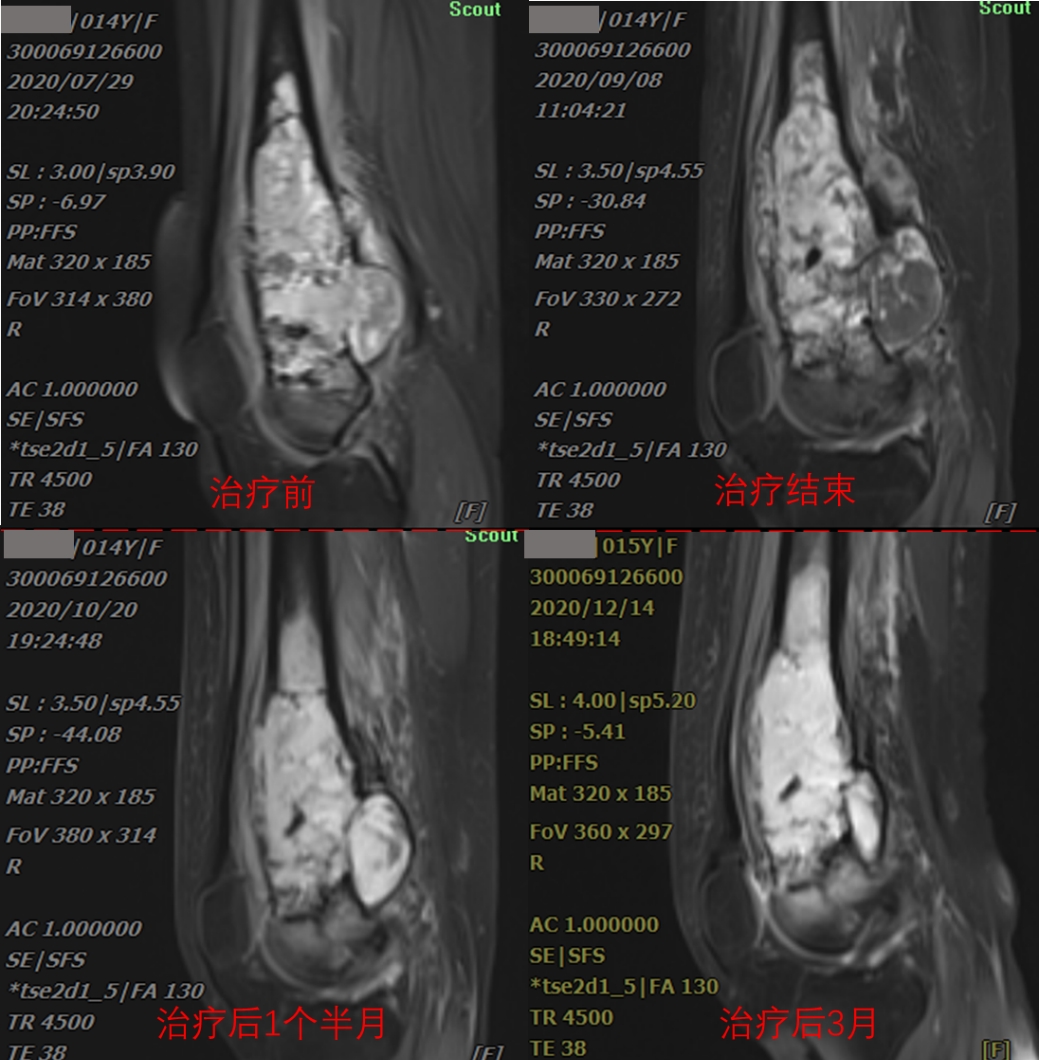

The patient, a 14-year-old female, was presented with the main complaint of "right thigh pain with mobility disorder for 3 months". CT examination indicated mild dilatant bone destruction in the right lower femur, accompanied by periosteum hyperplasia and soft tissue swelling, and neoplastic lesions (about 3.6x12.1x4.9cm in size) were mainly considered. Biopsy of the right femur mass was performed, and the biopsy results showed osteosarcoma (right lower femur). Diagnosis: osteosarcoma of right femur (cT2N0M0 Stage IIB KPS score: 70). The comprehensive treatment based on carbon ion radiotherapy was started on August 18, 2020. The tumor volume was 188.62cm3, and the heavy ion therapy was completed 12 times in total within three weeks. The treatment will end on September 3, 2020.

As can be seen from imaging data, tumor inactivation and slow absorption after treatment. According to international experience, it may take 1-2 years for huge sarcomas to be completely absorbed after inactivation. However, after heavy ion treatment, the purpose of limb preservation can be achieved, and anti-tumor immunity can be activated, and distant and side effects can be induced, which can effectively remove tumor tissue outside the tumor body. Combined treatment with chemotherapy and immunotherapy is expected to achieve a better effect, providing a new way for osteosarcoma patients. Through the observation of the treatment process of the patient's osteosarcoma, it can be seen that 1 and a half months after the end of heavy ion treatment of osteosarcoma, the local edema of the tumor was obvious, and 3 months after the end of the treatment, the local tumor was significantly smaller than before the treatment, the patient's symptoms were significantly relieved, and the tumor was well controlled locally. During the treatment, there was no obvious pain, no obvious edema in the lower extremities, and no obvious radiotherapy reaction in the local skin.